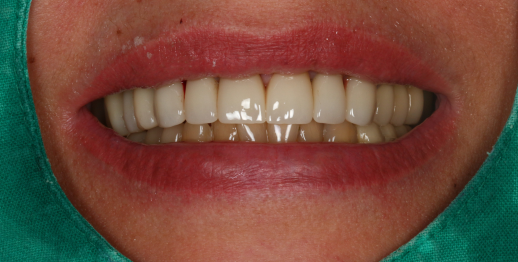

Upper jaw dental implants and bone graft

55 y.o, Russia

Operating dentist: Roh Hyun Ki